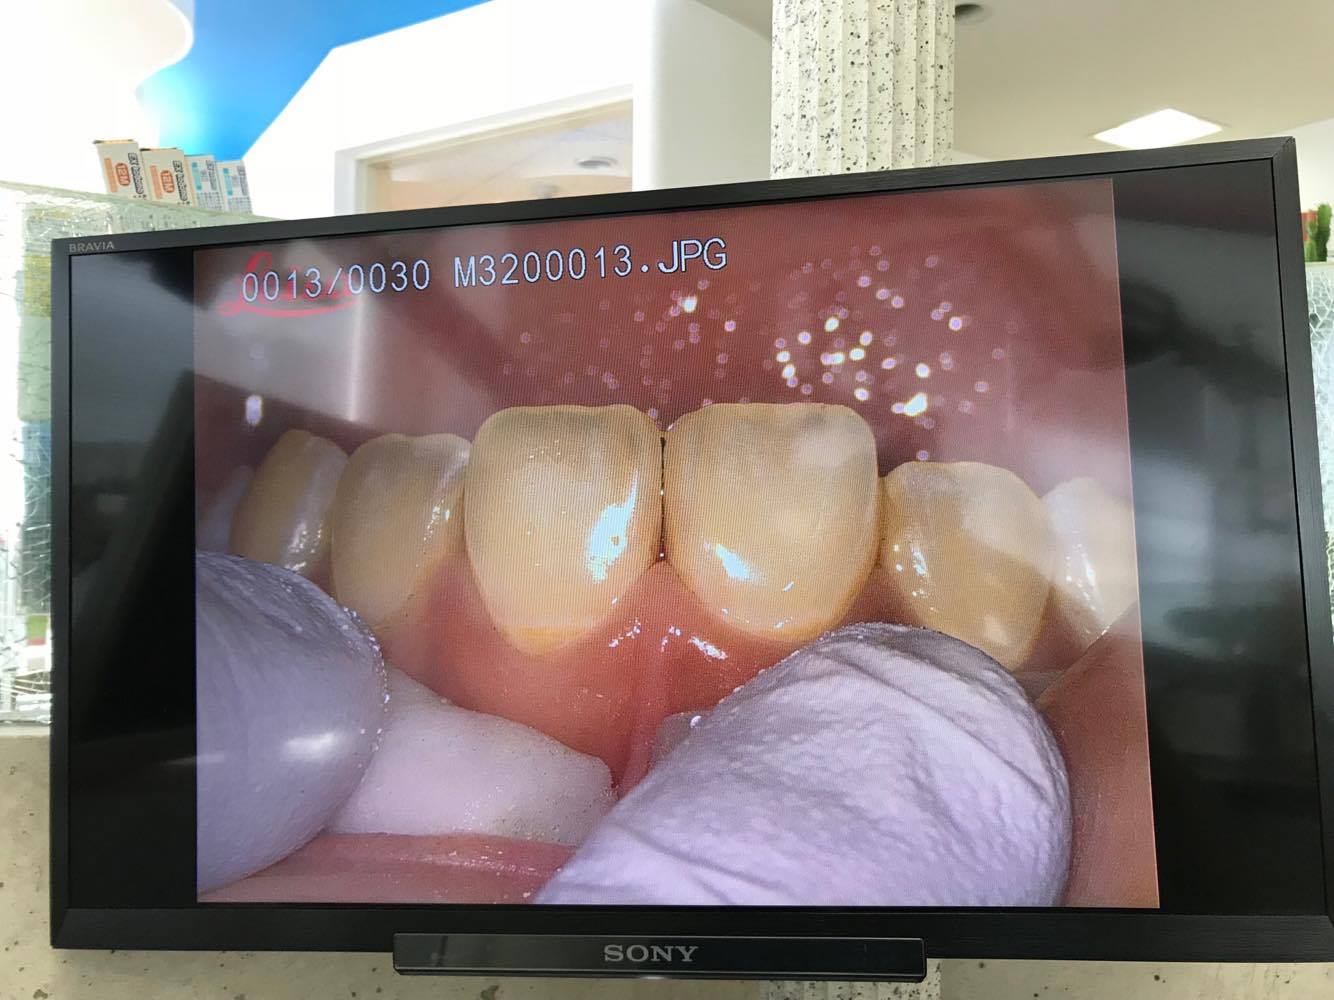

上顎前歯部正中にコンポジットレジン充填の不揃いを認めます。

写真は術前